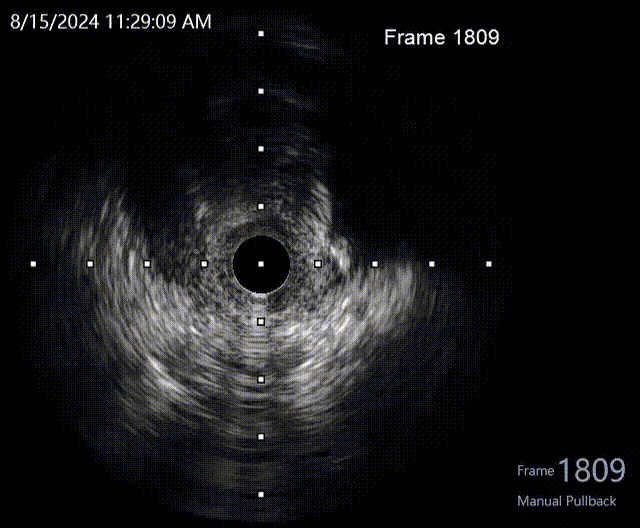

撤出微导管,1.5mm球囊扩张LAD近段后,送入IVUS导管,明确LAD近段导丝是否走行在真腔内,观察LAD在D1分叉处的开口位置,指导CTO导丝的进攻方向。

回撤显示导丝位于真腔,分叉处CTO入口在11-12点处,遂在X线影像中标记入口位置。

再次送入IVUS超声导管至LAD远段回撤,结果显示导丝全程位于真腔,近端见钙化及少量血肿。